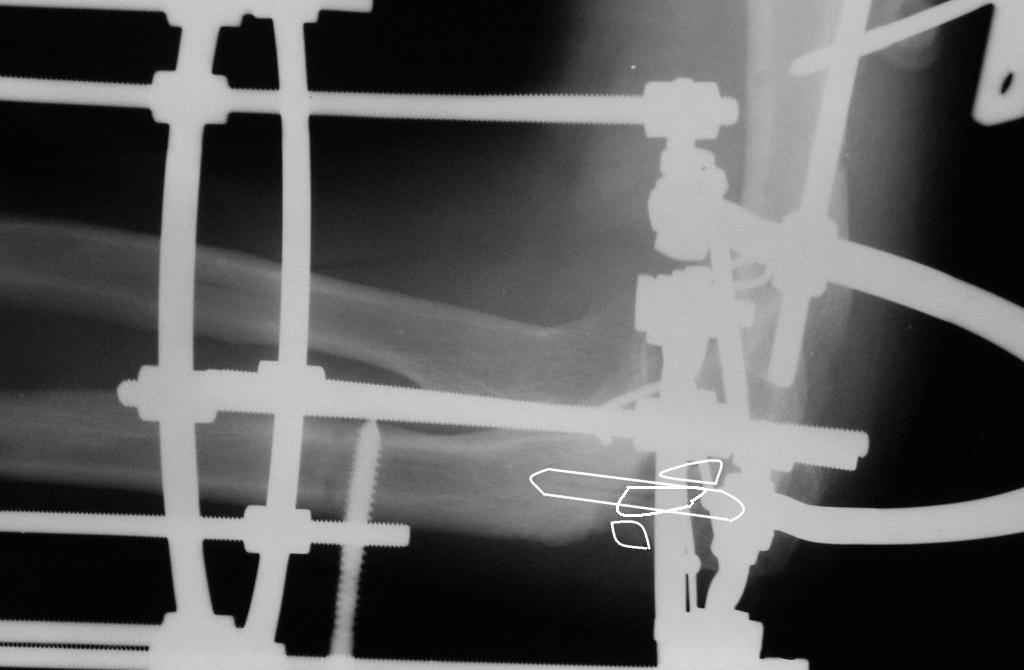

Коллеги! Сделана операция. Убрана рубцовая ткань, освежены концы до "кровяной росы", произведен релиз локтевого отростка и заднего отдела сустава - прошел до венечного отростка. После адаптации отломков выяснилось, что полное сопоставление происходит только на 1/4 периметра. Уложены аутотрансплантаты взятые из крыла подвздошной кости. Приведена схема. Через локтевой отросток проведены две спицы с упорными площадками с разбросом в 1 см, закрепленные на отдельном полукольце. Дана компрессия. Пятые сутки, рана заживает первичным натяжением. Выписываю. На 14 сутки буду пробовать движения.